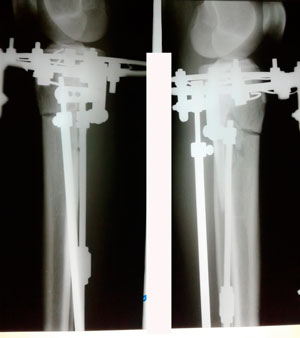

Исходник - 21 год. Бишкек.

Дата операции 30.06.2020

в процессе круток

на фиксации